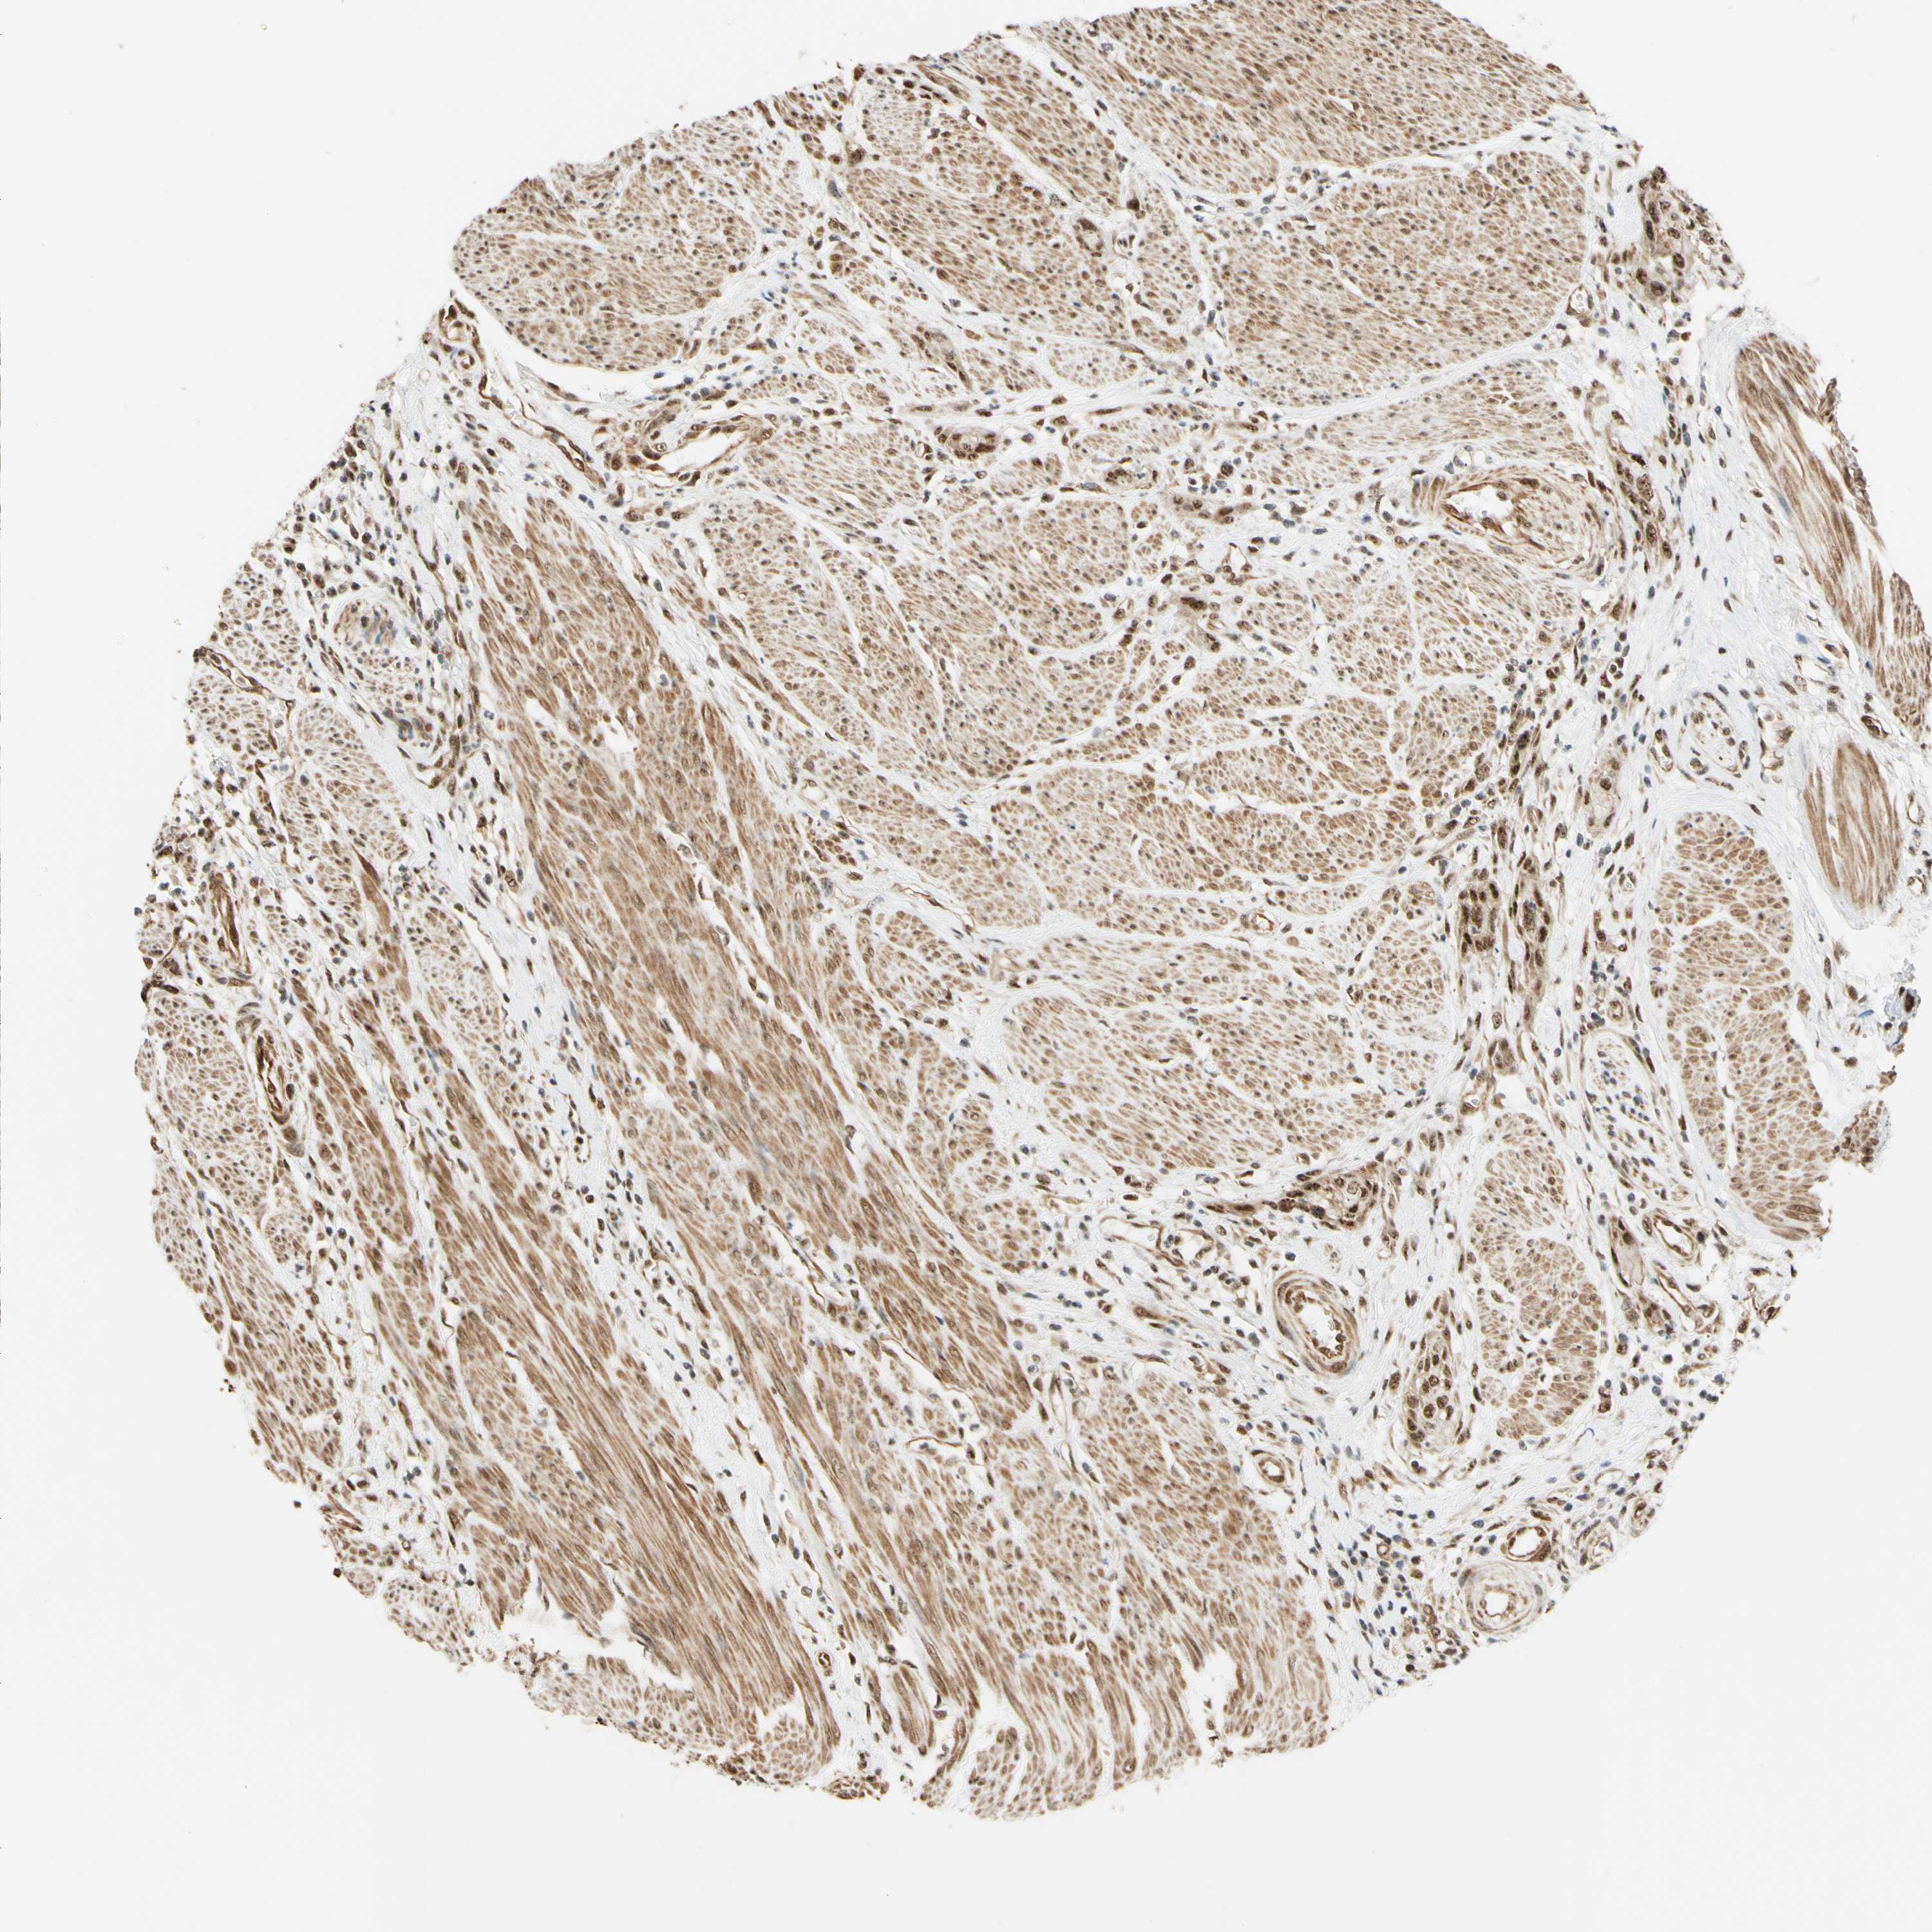

UROTHELIAL CANCER - Protein expressioni

A mouse-over function shows sample information and annotation data. Click on an image to view it in a full screen mode. Samples can be filtered based on level of antibody staining by selecting one or several of the following categories: high, medium, low and not detected. The assay and annotation is described here.

Note that samples used for immunohistochemistry by the Human Protein Atlas do not correspond to samples in the TCGA dataset.

Antibody stainingi

Antibody staining in the annotated cell types in the current human tissue is reported as not detected, low, medium, or high, based on conventional immunohistochemistry profiling in selected tissues. This score is based on the combination of the staining intensity and fraction of stained cells.

Each image is clickable and will lead to virtual microscopy that enables deeper exploration of all samples and also displays staining intensity scores, fraction scores and subcellular localization as well as patient and tissue information for each sample.

Antibody HPA011352

Antibody CAB012273

Staining

High

Medium

Low

Not detected

Intensity

Strong

Moderate

Weak

Negative

Quantity

>75%

75%-25%

<25%

None

Location

Nuclear

Cytoplasmic/membranous

Cytoplasmic/membranous,nuclear

Urothelial carcinoma, Low grade

Urothelial carcinoma, High grade